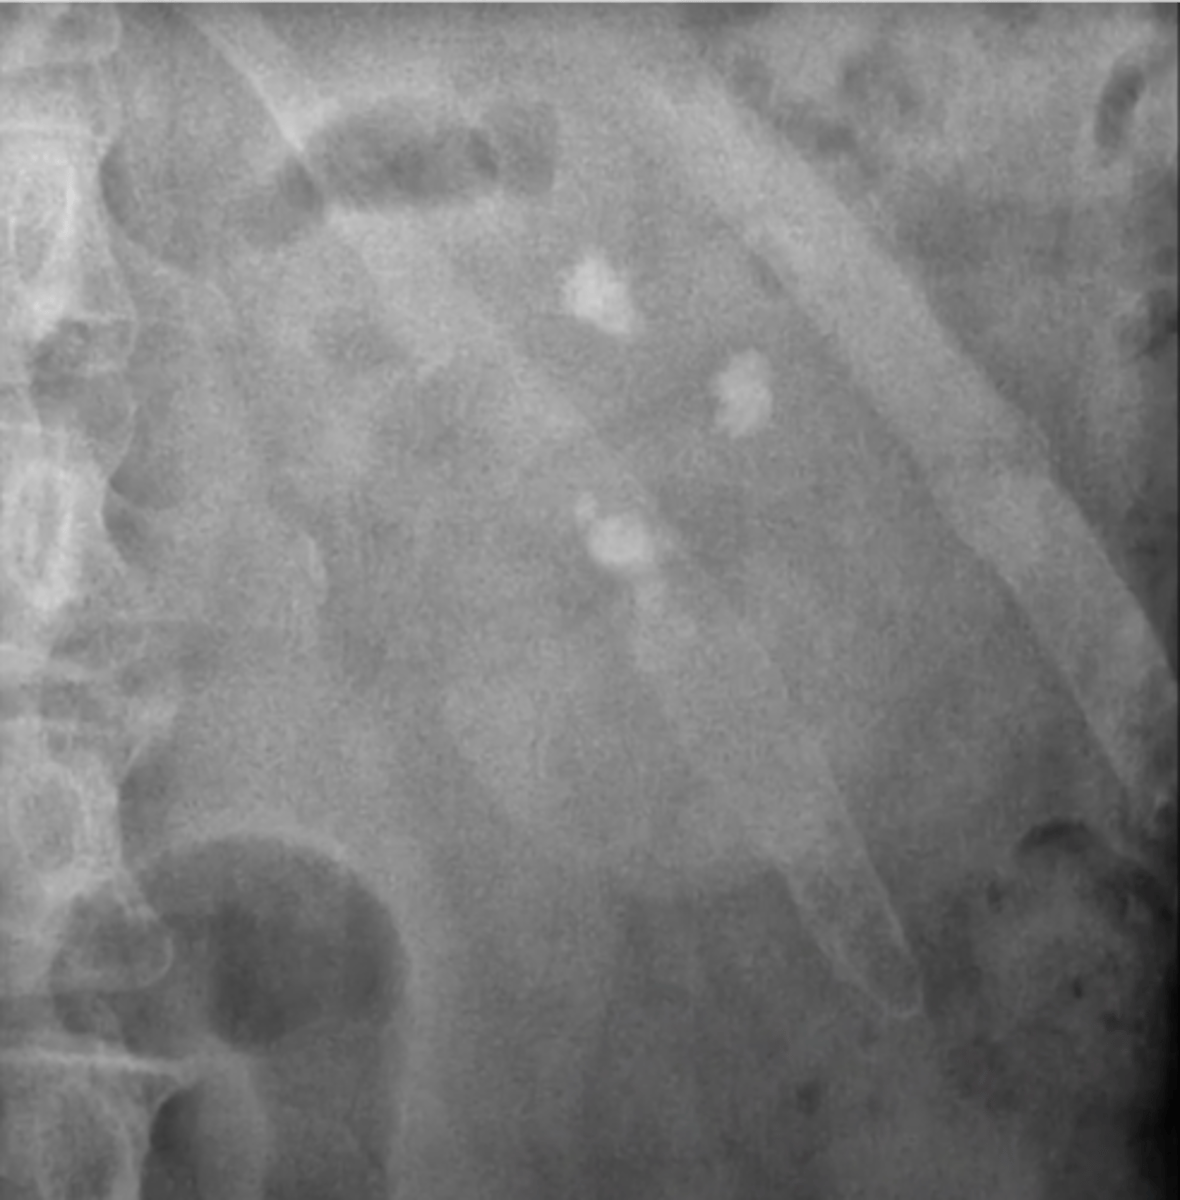

medullary nephrocalcinosis